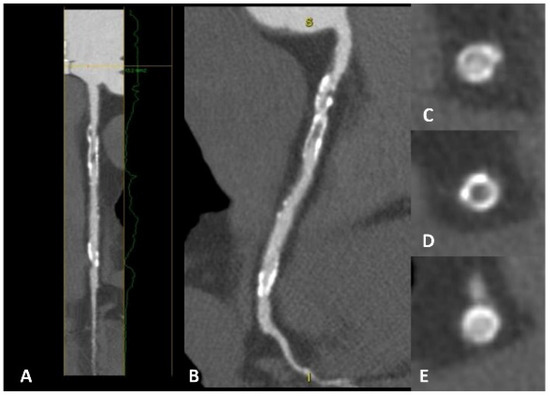

Coronary CT is a well-known non-invasive technique for evaluating patients with CAD. In the context of secondary prevention, this approach provides the initial valuable data required for effectively stratifying these patients (Figure 5). Phenotypic characterization of the plaque aims to define whether a plaque is at high risk. Positive remodeling, spotty calcification, low attenuation plaque, and the Napkin-ring sign are indicators of a high-risk plaque. Furthermore, lesion volume progression is an independent predictor of MACE in subjects with unrevascularized non-culprit intermediate stenosis (50–69%) [53]. In patients with ACS, the characterization of non-culprit plaques is central to risk assessment and management over time. Non-culprit plaques with >50% luminal narrowing or with a high plaque burden are associated with a significant risk of MACE [54]. In addition, coronary CT-derived fractional flow reserve adds prognostic information on non-culprit plaques in patients with ACS. Indeed, a CT-derived FFR value ≤ 0.80 is a predictor of future MACE (HR 1.56, 95% CI 1.01–2.83, p = 0.048) [55]. Furthermore, plaque burden progression is associated with a high incidence of MACE in individuals with stable angina [56]. Data are also emerging on the useful role of coronary CT in the risk assessment of individuals with stroke. CAD detection in these patients is independently associated with MACE [57,58], adding prognostic value over the CAC score [59]. Finally, van’t Klooster et al. reported interesting data on the incremental value of CAC, thoracic aortic calcium, and heart valve calcium scores in patients with established CVDs such as coronary heart disease, cerebrovascular disease, and/or PAD [60]. The CAC score improves the performance of risk prediction models and adds prognostic value to the prediction of future MACE in patients with stable CV disease (HR 1.35, 95% CI 1.15–1.58).

Figure 5.

A patient with previous percutaneous revascularization of the right coronary artery, with cardiac CT showing evident in-stent restenosis in both long-axis view (panels A,B) and short-axis view (panels C–E). In panel (D), a clear hypodensity is evident inside the stent lumen compared with panels (C,E).